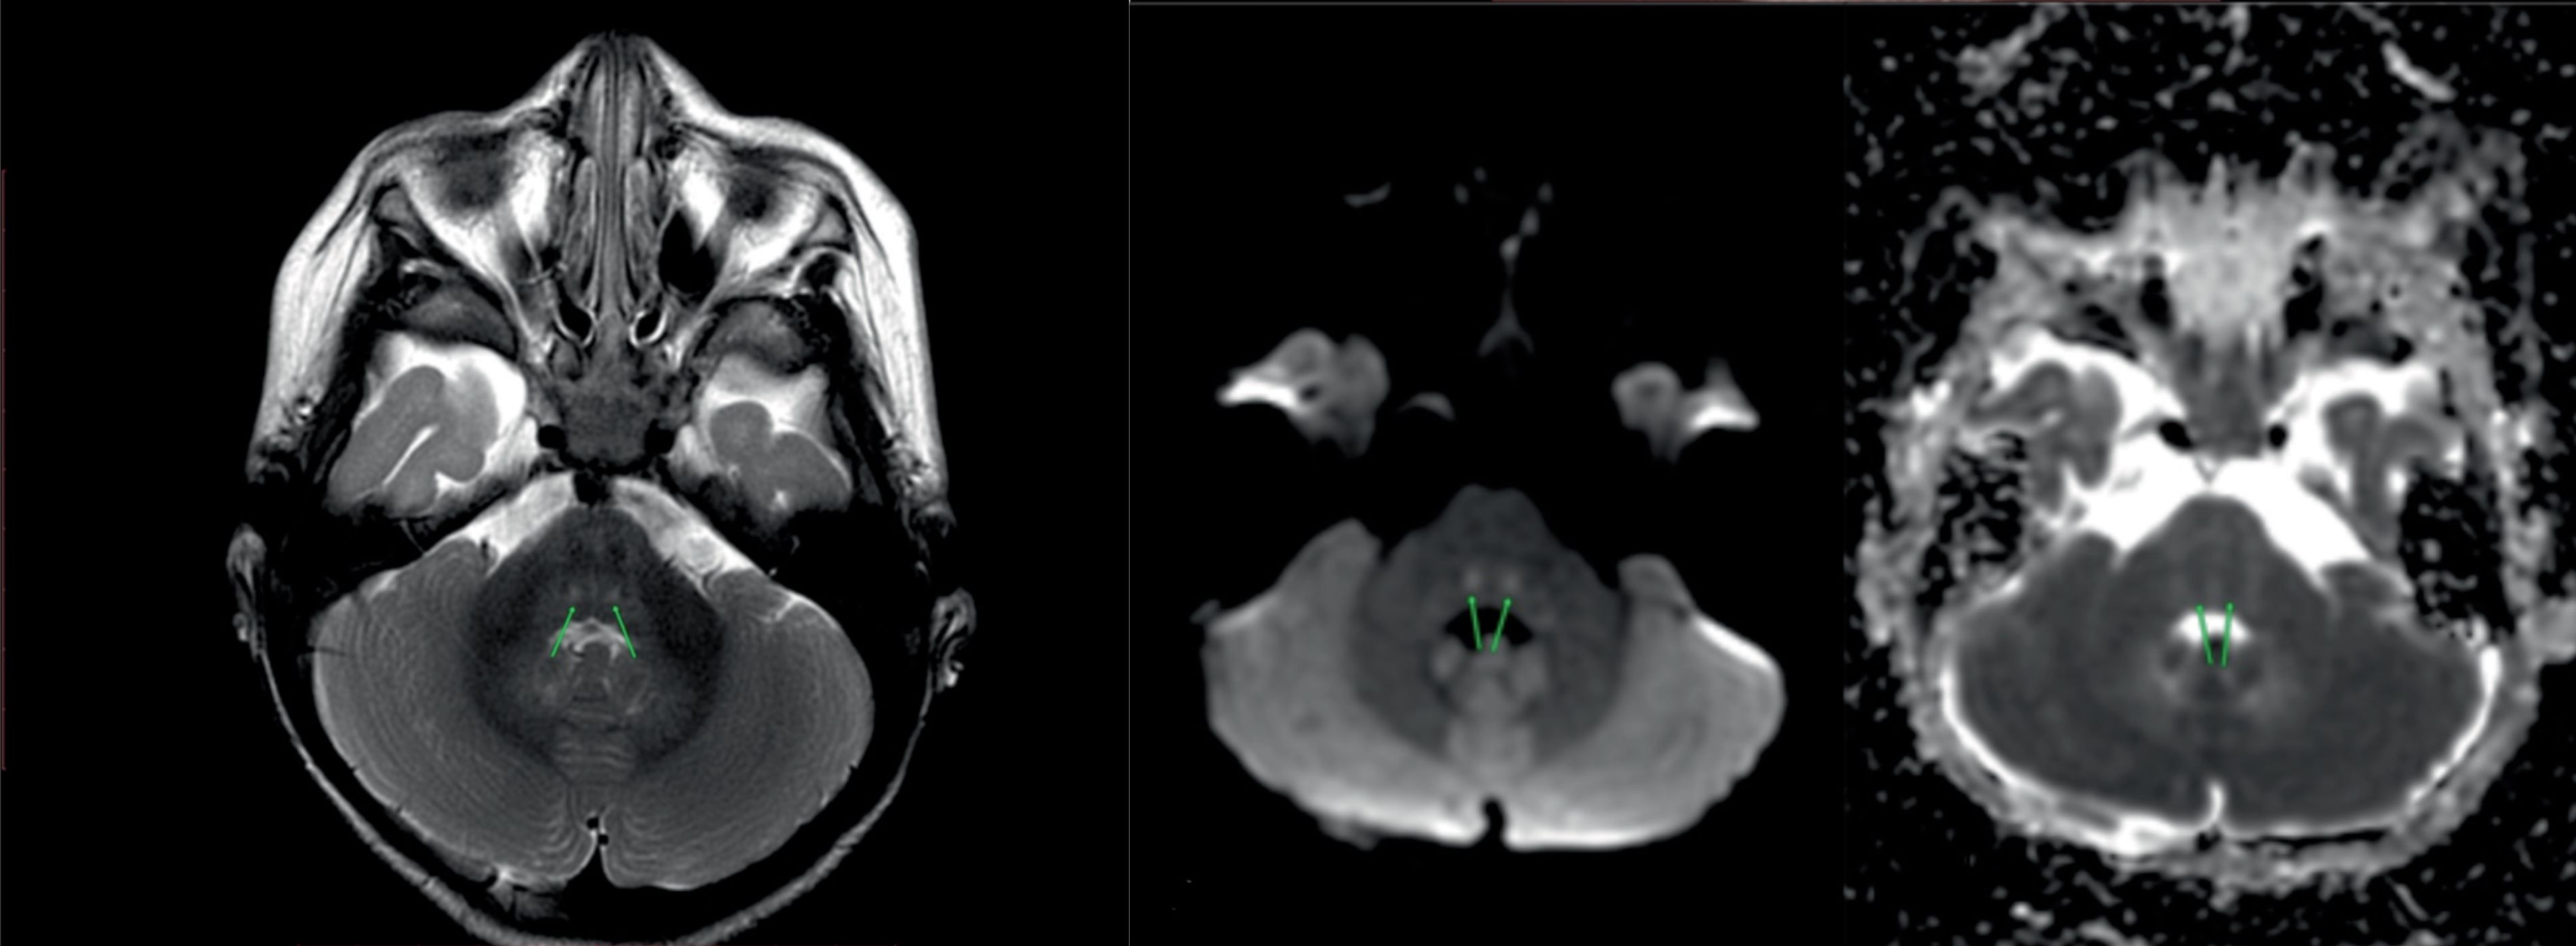

Магнитно-резонансная (МР) томография головного мозга: МР-исследование головного мозга проведено в Т1- и Т2-взвешенном изображении и FLAIR в сагиттальной, аксиальной и фронтальной проекциях, а также в DWI, SWAN.

На МР-томограммах головного мозга срединные структуры не смещены. Извилины больших полушарий сформированы правильно. Явных признаков дисгенеза кортикальной пластинки не выявлено. Симметрично в проекции центрального покрышечного тракта отмечаются участки повышения МР-сигнала на Т2-ВИ, слабого понижения — на Т1-ВИ, с признаками ограничения диффузии (без динамики).

На фоне незавершенной миелинизации белого вещества теменных отделов нельзя исключить очаговые изменения, без признаков ограничения диффузии. На остальном уровне в веществе больших полушарий и мозжечка, а также краниовертебрального перехода, очагов патологически измененного МР-сигнала, зон кровоизлияний, а также новообразований не выявлено. Мозолистое тело сформировано.

Желудочковая система: боковые желудочки симметричны, не расширены. Третий и четвертый желудочки не деформированы.

Субарахноидальное пространство лобно-височных отделов умеренно расширено (без динамики). Турецкое седло обычной формы и размеров. Гипофиз не увеличен. Структура аденогипофиза однородная. Дифференциация на адено- и нейрогипофиз четкая. Перекрест зрительных нервов и воронка гипофиза не смещены. В области орбит видимых патологических изменений не выявлено. Каналы и перекрест зрительных нервов не деформированы, ход и калибр не изменены.

Заключение: МР-картина симметричного поражения центрального покрышечного тракта (нельзя исключить метаболический генез). МР-данных за объемное поражение вещества головного мозга не получено (рис. 4). По сравнению с результатом МРТ от 21.04.2020 г. — без динамики. Рекомендовано: динамическое МР-наблюдение.

Рис. 4. МРТ головного мозга пациентки С.

а — Т2-взвешенное изображение в аксиальной плоскости: симметричные участки гиперинтенсивного сигнала в области покрышечных путей; б — диффузионно-взвешенное изображение: гиперинтенсивный сигнал; в — карта измеряемого коэффициента диффузии: гипоинтенсивный сигнал.

Fig. 4. MRI of the brain of patient C.

a — T2-weighted image in the axial plane: symmetrical sections of the hyperintensive signal in the area of the tire pathways; b — diffusion weighted image: hyperintensive signal; c — map of the measured coefficient of the diffusion: hypointensive signal.